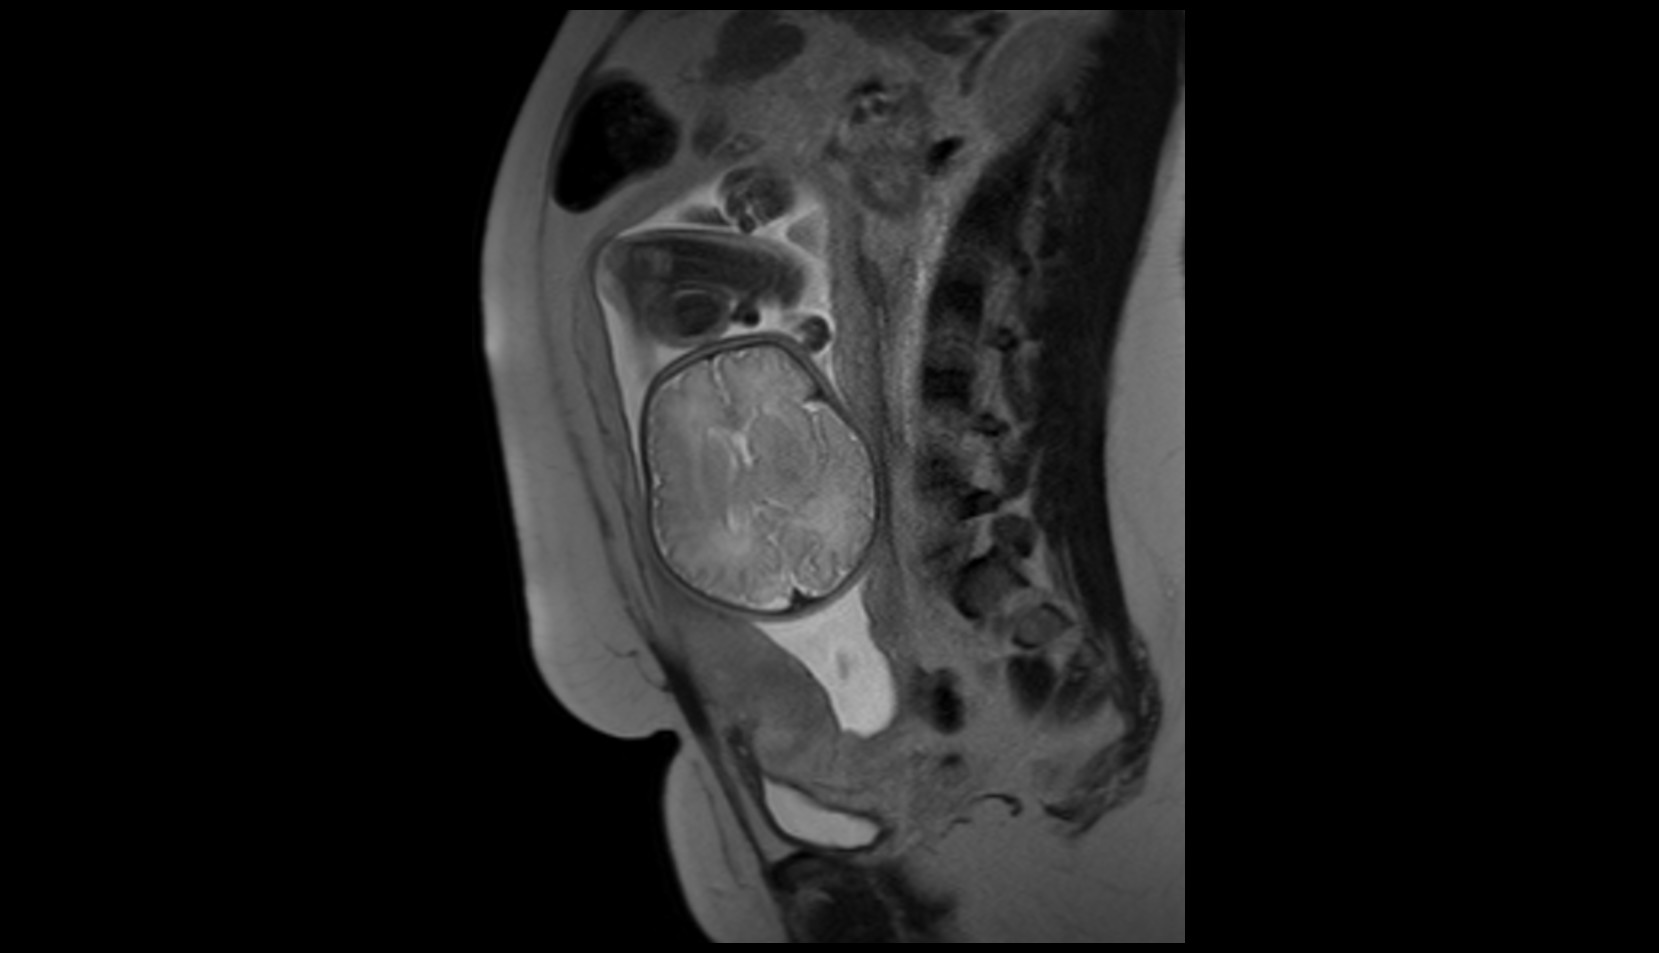

- Placenta

- Uterus (pregnancy)

- Amniotic fluid

- Umbilical cord

- Cervix in Pregnancy

- Vagina in Pregnancy

- Fundus of uterus in pregnancy

- Fetal brain

- Fetal cervical spine

- Fetal thoracic spine

- Fetal lumbar spine

- Fetal spinal cord